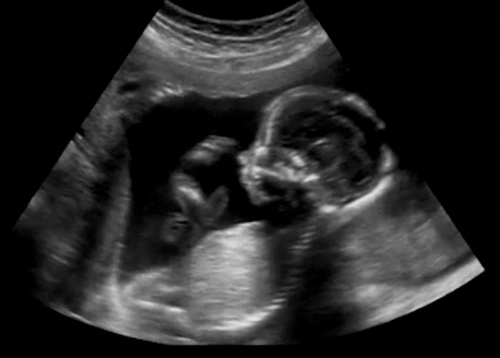

羊水の量には個人差があるものの、正常値から外れた場合、妊娠経過の観察や分娩の管理が必要になることがあります。そのため、妊婦健診時には経腹超音波検査(エコー検査)を行い、羊水ポケット(AFP)、羊水インデックス(AFI)、最大羊水深度(MVP)といった計測により羊水量を評価します。

羊水ポケットは、子宮壁から胎児までの距離がもっとも広い場所に円を描き、その直径が何cmかを測定します。2cmに満たないと羊水過少、8cm以上で羊水過多と診断されます。羊水インデックスは子宮を4つに区切り、それぞれの羊水最大深度を測ってその合計値であらわします。AFIが5cm未満は羊水過少、AFI24cm以上が羊水過多です。

羊水検査ではダウン症候群やターナー症候群などの染色体異常を調べ、遺伝子疾患や開放性神経管奇形を検査することもあります。検査方法は「羊水穿刺(ようすいせんし)」をとり、細い注射針を羊膜に挿入して羊水を20mLほど採取します。検査の時期は妊娠15~16週以降です(※1)。